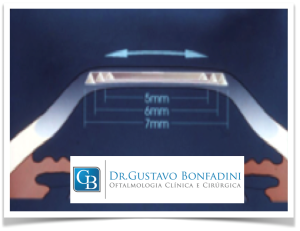

1) O que é e qual objetivo do Segmento de Anel (anel intra estromal)?

O anel intracorneano (Kerarings ®, Anel de Ferrara ® ou Intacs ®) é uma órtese transparente composto de um material inerte e biocompatível ao olho, de formato semicircular, de espessuras e diâmetro variáveis.

O objetivo do anel é regularizar e diminuir a curvatura corneana, e consequentemente melhorar a visão. Além disso, esse dispositivo é capaz de diminuir ou corrigir os erros de refração da Córnea de um paciente com Ceratocone.

A melhor indicação de tratamento com uso do anel corneano é no estágio moderado do Ceratocone, pois tem como objetivo tentar melhorar a estrutura da córnea e regularizar as deformações corneana, e tentar corrigir ou diminuir os erros de grau associados a esta córnea. O anel intracorneano é fabricado a partir do PMMA (polimetilmetacrilato), material comprovadamente inerte, biocompatível, não havendo risco de rejeição, pois este material é utilizado há décadas na fabricação de implantes intra-oculares.

Dr. Gustavo Bonfadini, explica que é aplicada anestesia local por meio de colírio, sem necessidade de internação. Atualmente este procedimento é idealmente realizado por meio de um Laser de Femtosegundo. Com o uso do Laser, não há corte com bisturi, fazendo com que a incisão seja criada a partir de uma fotodisrupção (separação) das lamelas da córnea, confeccionando assim um túnel no interior da Córnea. Exatamente conforme planejado pelo cirurgião especialista em córnea, conferindo uma maior previsibilidade e eficiência no implante do anel.

Em seguida, acontece o implante de 1 ou 2 seguimentos de anel. A cirurgia dura em média 30 minutos. Os segmentos vão tentar o aplanamento do ápice da córnea tentando deixá-la o mais próximo do natural. Esta técnica é reversível, sem danos para a córnea, e não é uma técnica refrativa, ou seja, o paciente deverá utilizar óculos ou lente de contato após a cirurgia de Ceratocone.

8) Qual a diferença de colocar 1 ou 2 anéis?

Conforme o estágio de evolução do Ceratocone, sua alteração na córnea, por exemplo, se ele é mais inferior ou mais central, o médico oftalmologista especialista em córnea vai usar um normograma para decidir se vai usar 1 ou 2 anéis e qual a posição deles na córnea. Ou seja, é um critério técnico.